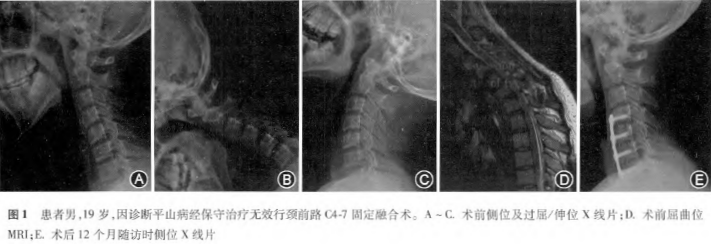

方法 回顾性分析自2006年10月至2014年1月北京大学第三医院接受颈前路钛板固定融合术治疗的平山病患者资料共46例。采用Odom评分评价患者手术治疗效果。